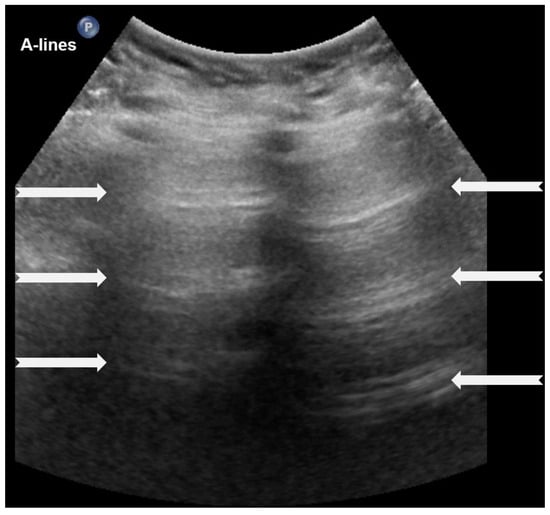

A-lines are horizontal, bright, echogenic lines that appear at equal intervals below the pleural line, running parallel to it (Figure 1). They are reverberation artifacts caused by the reflection of ultrasound waves between the pleura and the ultrasound probe. Although their presence typically indicates well-aerated, healthy lung tissue, A-lines can also be seen in certain pathological conditions, such as pneumothorax, where free air is present. Thus, A-lines are not always necessarily a sign of normal, healthy lungs [5,6,12,13,14,15,16].

A-lines: Horizontal, bright, echogenic lines at equal intervals below the pleural line, running parallel to it. A-Lines are one of the main (basic) artifacts in LUS.